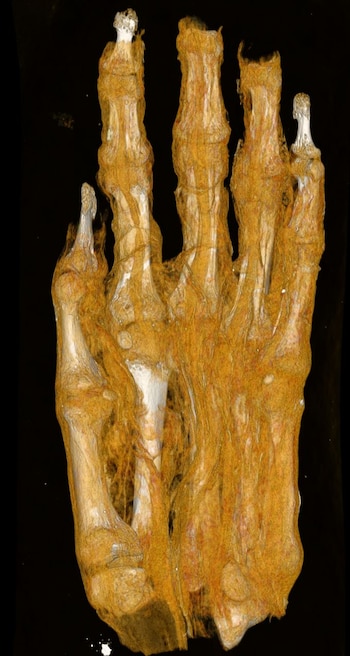

El uso del nuevo escáner ha permitido corregir errores de identificación en piezas que, durante décadas, habían sido mal catalogadas. Un caso paradigmático es el de un bulto momificado que fue considerado primero como una cabeza humana y luego como una posible momia de ave.

Solo las tomografías recientes comprobaron que se trataba de un pie adulto.

“A veces ni los expertos aciertan a la primera. Una muestra, antes atribuida a una cabeza humana o un pájaro, resultó ser el pie de un adulto”, reconoció la curadora principal Krisztina Scheffer.

El equipo también examinó una mano momificada con el objetivo de estimar, a partir del tamaño y la morfología ósea, la edad y el sexo del individuo.